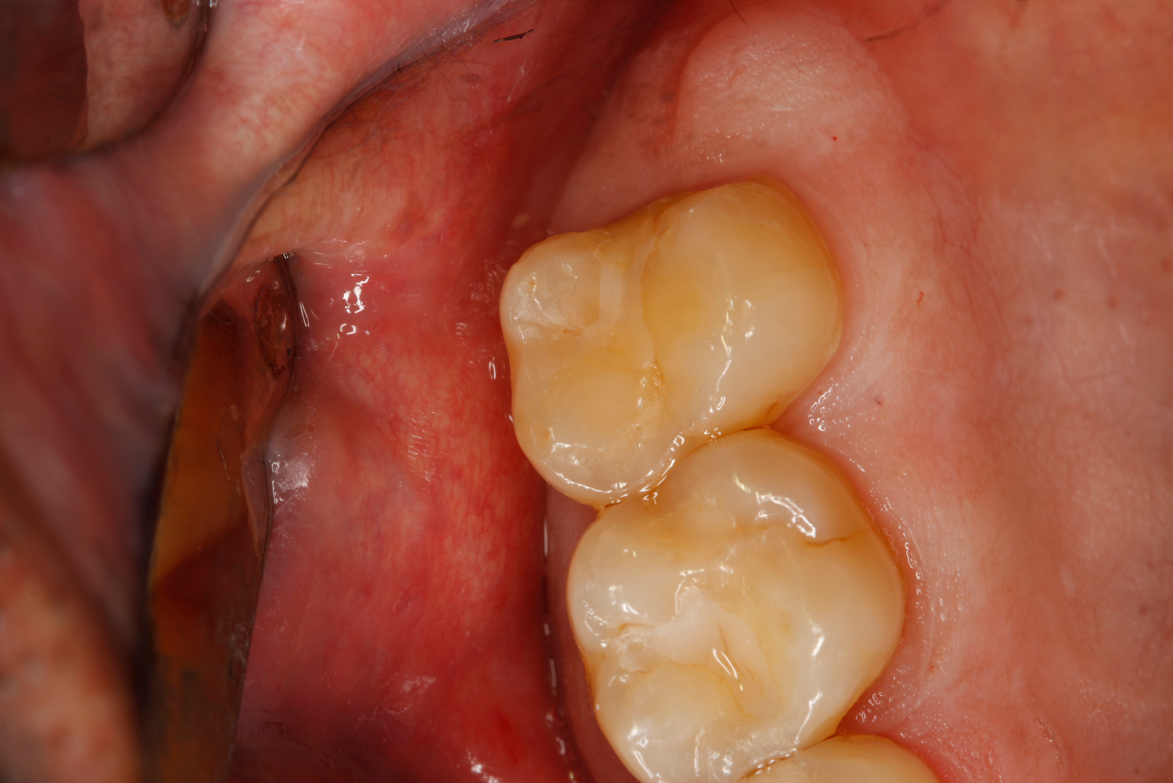

Fig 45. Finished restoration, ready for endodontic entry.

Fig 46. Close-up of polished surface.